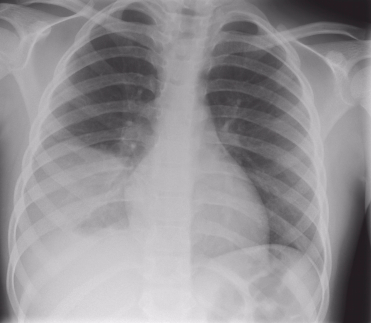

Chụp X-quang ngực, điện tâm đồ (EKG) và xét nghiệm nước tiểu,nuôi cấy máu và đờm để thiết lập chẩn đoán và loại trừ các nguyên nhân khác.